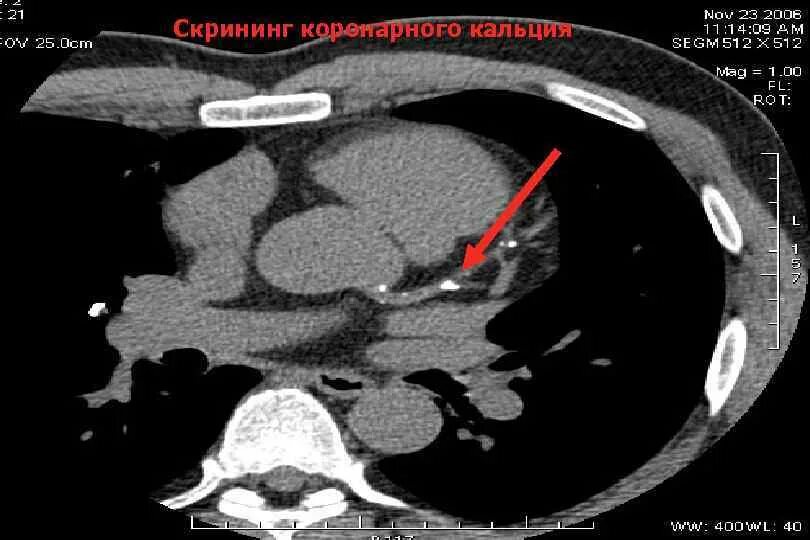

Скрининг кт